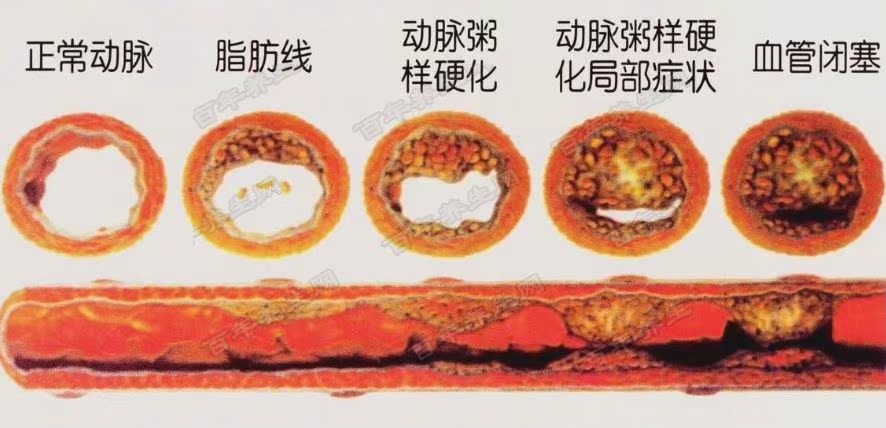

4.动脉硬化:

动脉硬化会导致大脑和肌肉缺血、缺氧,造成面部肌肉松弛,加上老年人吞咽能力减弱,从而导致睡觉哦流口水。如果老年人睡觉时爱流口水,那么即使没有口角歪斜、眼睛闭合不严等症状,也应当尽快到医院接受检查。重点检查是否存在“三高”情况,即高血压、高血脂和高血糖,做到早发现,早治疗。